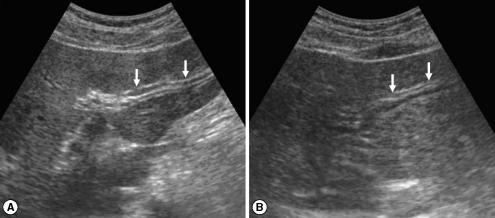

In the initial (pre-treatment) sonography of the 83 cured patients after treatment, DDIHD, IPDE, and FEFGB were found in 82 (98.2%), 42 (50.6%), and 32 (38.6%), respectively (Table 3). After treatment, DDIHD, IPDE, and FEFGB were found in 80 (96.4%), 45 (54.2%), and 17 (20.5%), respectively. DDIHD was improved in 3 (Fig. 1), aggravated in 1, and unchanged in 79 patients. IPDE was improved in 5 (Fig. 2), aggravated in 8, and unchanged in 70 patients. FEFGB was improved in 20 (Fig. 3), aggravated in 5, and unchanged in 58 patients. Neither DDIHD nor IPDE showed significant changes (P = 0.625 and P = 0.581, respectively). However, FEFGB revealed a statistically significant improvement (P = 0.004) (Table 3).